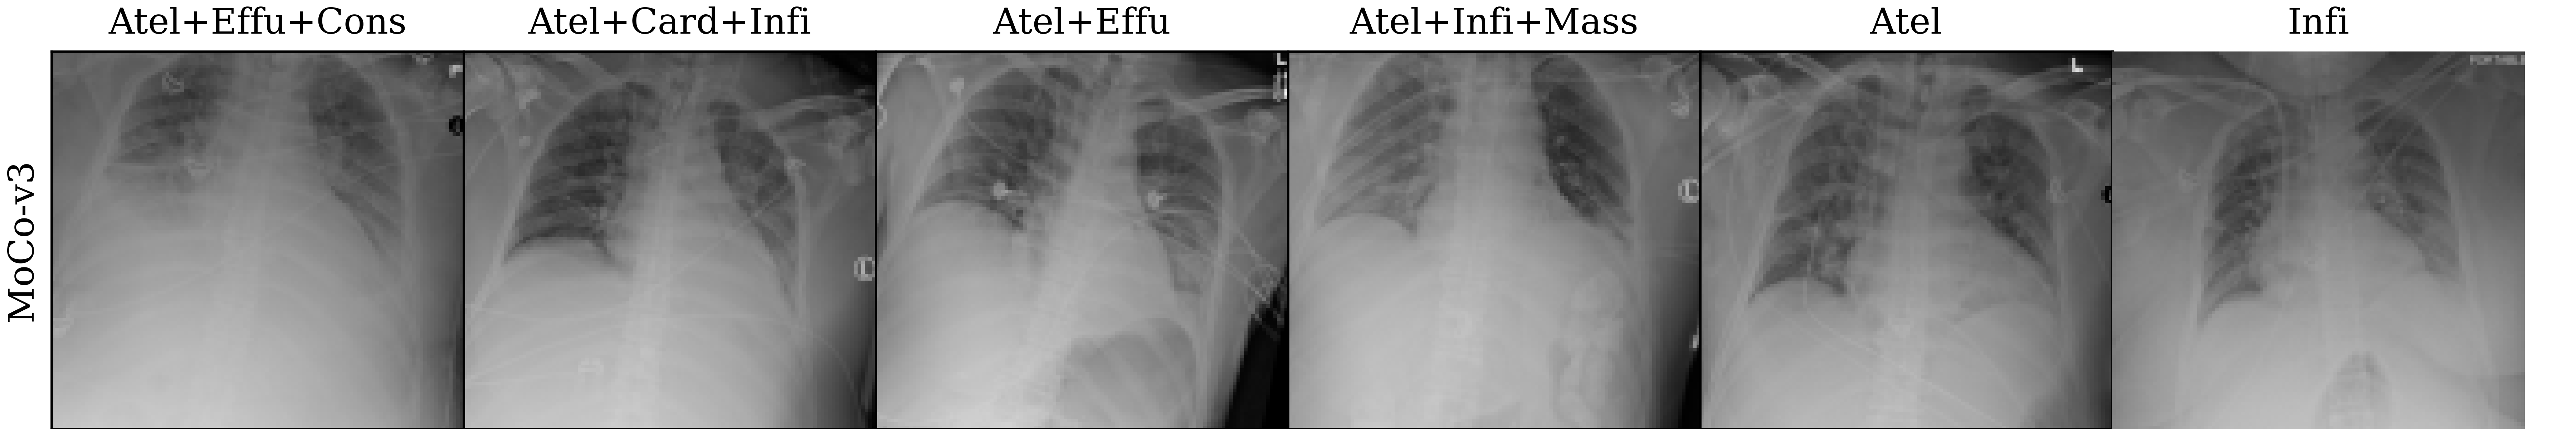

Lastly, we visualize the nearest neighbors in the embedding space of MoCo-v3 and MAE pre-trained models to yield insights into the pre-trained representations. To this end, we extract the last layer representations (after the layer norm) for both the train and test sets of ChestXray14. For each image in the test set, we compute the 5 nearest neighbors from the train set. The results are visualized in Figure 4, which reveals that the nearest neighbors of both MoCo-v3 and MAE largely preserve the overall shape of the query image. Additionally, we also perform a quantitative analysis by assigning the label of the nearest neighbor as the prediction for the query image. Under this nearest neighbor classification setting, MoCo-v3 has a slightly higher mAUC than MAE (52.7 vs 52.3), indicating that its pre-trained features are more linearly separable. This finding is in line with the observations made by He et al. (2022), who observed that the MoCo-v3 features are more linearly separable than MAE features. However, it is worth noting that despite MAE features being less linearly separable than MoCo-v3 features, the former captures more powerful non-linear features. This translates to stronger downstream models when the networks are fine-tuned instead of being used as fixed feature extractors, as evidenced by the superior fine-tuning results presented in Section 4.1.